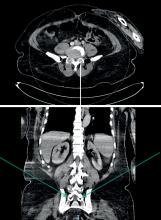

Le bypass gastrique en Y (RYGB) et, dans une moindre mesure, la gastrectomie en manchon (SG), modifient de façon significative la structure anatomique du tractus gastro-intestinal. Or, ce raccourcissement intestinal peut altérer l’absorption des contraceptifs oraux contenant un composant œstrogénique, métabolisé dans la paroi intestinale haute. L’efficacité de la pilule contraceptive pourrait donc être réduite.